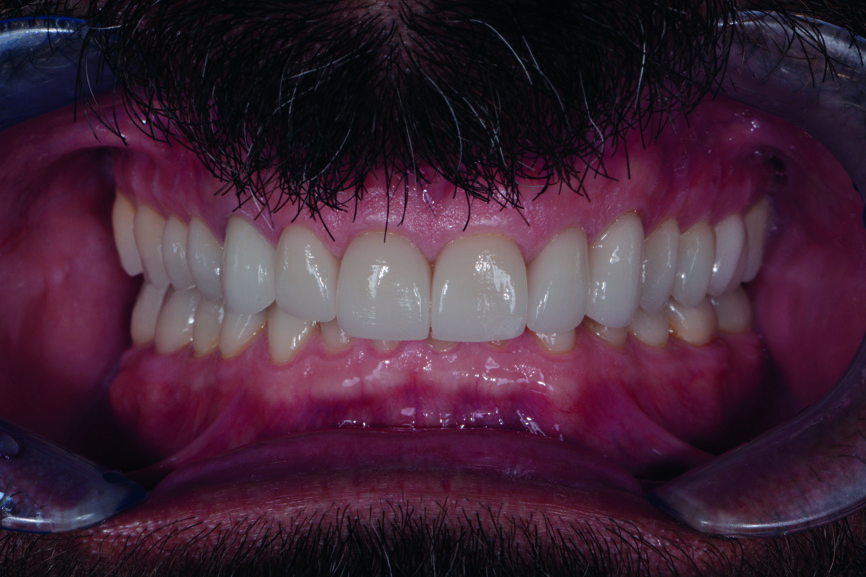

En 2015, un patient de 47 ans se présente au cabinet en raison d’une douleur au niveau de l’ATM. Il a également une préoccupation d’ordre esthétique, car une partie de la facette posée sur l’une des incisives centrales supérieures est fracturée (Figs. 1–3). L’analyse clinique et radiographique (Fig. 4) indique une perte de DVO et de substance dentaire dues au bruxisme.

Fig. 1 : Photographie intraorale avant le traitement, prise de face.

Figs. 13 et 14 : Photographies intraorales après le traitement.

Figs. 16 et 17 : Photos de suivi en janvier 2021 montrant un résultat très stable sans aucun écaillage de la céramique et des avantages mécaniques constants mentionnés par le patient, tels que plus de céphalées de tension